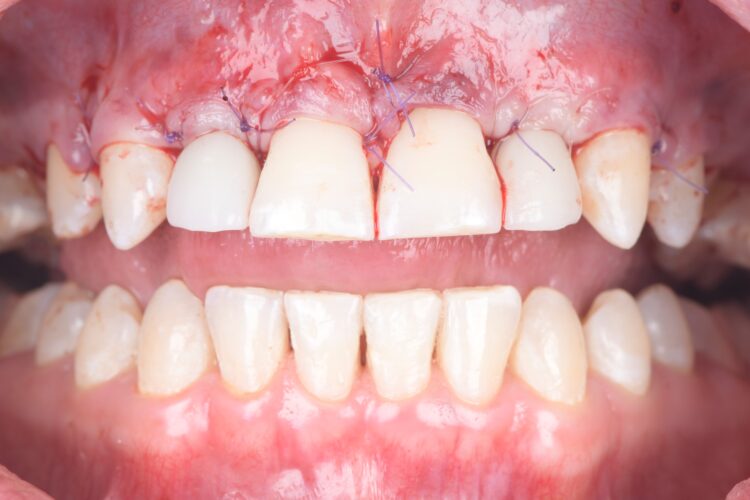

On the day of surgery, a split-thickness envelope flap was raised. Two CONELOG® Progressive-Line implants were placed through the surgical guide in the pre-determined lateral incisor positions. Soft tissue augmentation was performed simultaneously with the implant placement, and the site was sutured and closed without tension. The implants were immediately loaded using provisional crowns that were pre-fabricated in the lab.